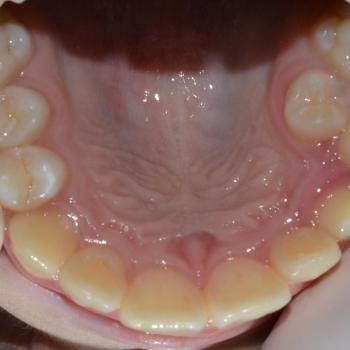

Ádám és szülei, mint oly sokan az alsó és felső fogív torlódása miatt kerestek fel. Már az első találkozásunk alkalmával egyértelművé vált, hogy a torlódást nem egyszerűen a szűk fogív, sokkal inkább a fogak macrodontiája, azaz a fogak túlzott mérete okozza. Ezzel párhuzamosan fény derült a felső középvonal balra tolódására és mindkét oldalon harapási eltérésre is, mely az őrlők területén Angle II. osztályú, míg a bal felső szemfognál Angle III. osztályú volt.

A kezelés eredményeként megszűnt a torlódás, korrigálódott a harapási eltérés, illetve jelentősen javult a középvonal eltolódás is.